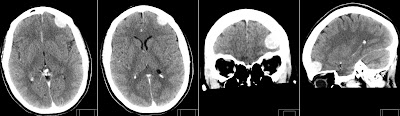

Incidental Meningioma found on Non Contrast CT (NCCT) scan of a patient after a small trauma. Note that this extraaxial tumor is rather difficult to detect on NCCT.

Measured density of Meningioma is just slightly hyperdense to adjacent normal brain parenchyma on NCCT. This makes Meningiomas sometimes difficult to detect.

After iv contrast is given Meningioma shows typical homogeneous intensive contrast enhancement. This is our standard C35 W70 brain CT window.

However note that tumor delineation is much better on a broader CT window with higher center value of C50 W150. This setting is also useful for detection of hemorrhage and pathology in the skull base region, especially after iv contrast.